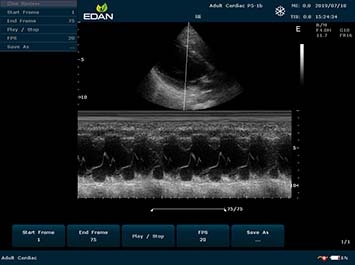

Качество визуализации:

- Тканевая гармоническая визуализация для высокой детализации

- Технология SCI для улучшенного контрастного разрешения

- Интеллектуальное подавление зернистости изображения

- Многолучевая технология с высокой частотой кадров

- Полный набор допплеровских режимов

- Триплексный режим для комплексной оценки

M-режим:

Да